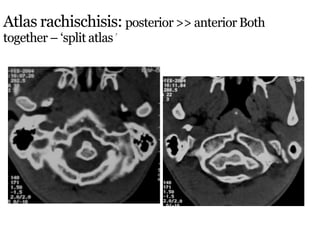

Atlas rachischisis: posterior >> anterior Both

together – ‘split atlas’

Atlas rachischisis: posterior>> anterior Both together – ‘split atlas’